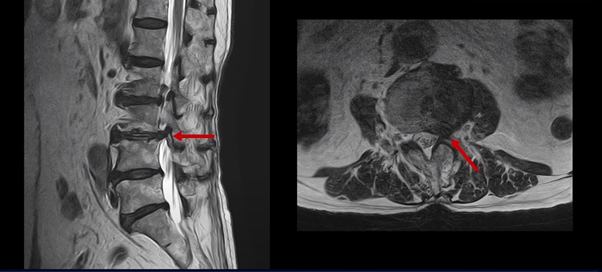

이 두 마디가 왼쪽 증상, 특히 허벅지 통증을 일으키는 원인으로 보입니다. 이렇게 여러 마디가 안 좋을수록, 또 고령일수록 수술하기가 더 까다로워지는데 또 큰 문제는 이 환자분은 근감소증이 심하게 진행된 상태로, 여기 MRI에서 보시다시피 허리 하부의 기립근 근육이 전부 지방으로 변해버려 근육 자체가 거의 없는 상태인 것입니다.

근육이 없는 근감소증 환자는 척추수술 후 예후가 더 안 좋은 것으로 알려져 있기 때문에 상담하신 정형외과에서도 수술 권유를 안 한 것으로 보입니다.

그런데 저희는 여러 영상을 통해서 디스크가 있건 협착증이 있건 근육의 역할이 가장 중요하고, 주변 근육이 아프지 않고 제 기능을 잘하면 협착증, 디스크, 전방전위증이 있어도 안 아프거나 훨씬 덜 아프다고 지속적으로 이야기하고 있습니다. 이것이 바로 협착증, 디스크, 전방전위증이 수술 없이 치료가 가능한 이유인 것입니다.